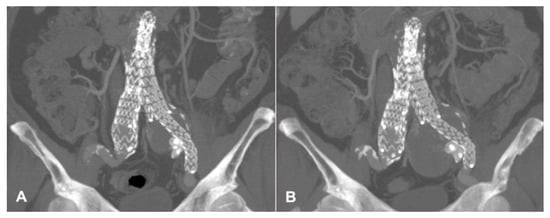

2. Case Presentation